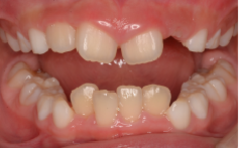

歯は削れば削るほど、もろくなります。歯の表面のエナメル質に無数のひびが入ったり、インレー(歯の詰め物)

(虫歯よりもかなり大きく削る)を装着すると、くさびのような働きをして、歯が割れてしまう事があります。

●大きく削ってインレーを詰めても細菌の取り残しがある→数年後、虫歯の再発